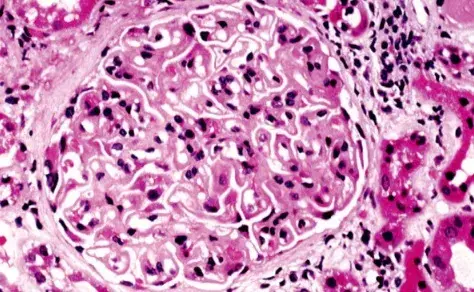

Nefropatia Membranosa: e se o paciente não responder ao tratamento inicial?

Nefropatia Membranosa: e se o paciente não responder ao tratamento inicial?

Como fazer o tratamento da Nefropatia Membranosa de forma prática!

Como fazer o tratamento da Nefropatia Membranosa de forma prática!